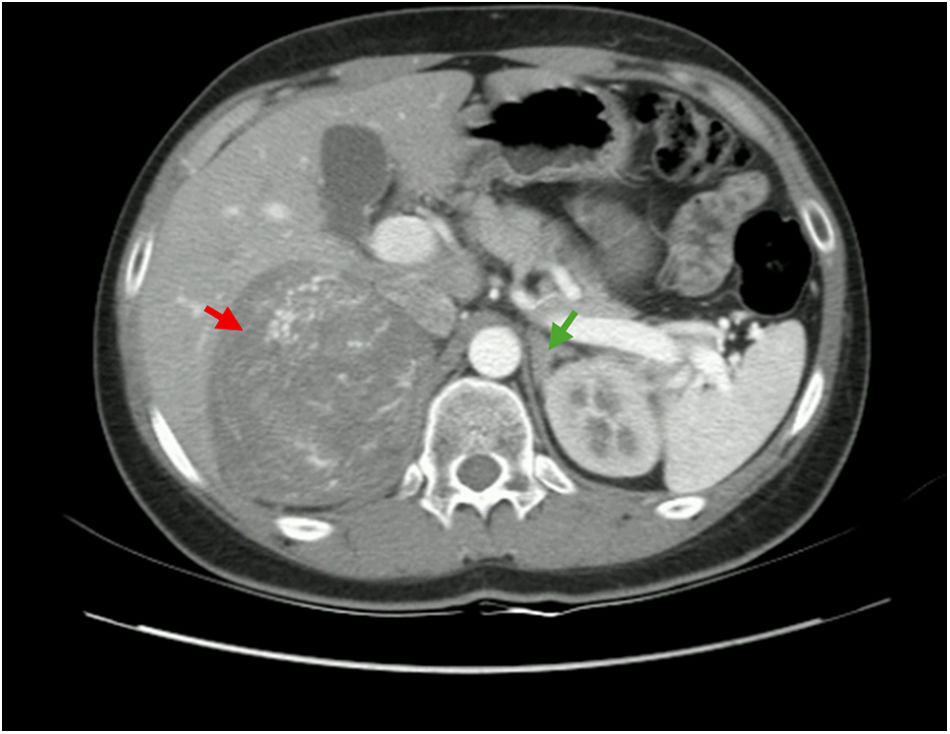

ACTH-producing pheochromocytomas are rare. Familial adenomatous polyposis (FAP), caused by mutations in the Adenomatous Polyposis Coli (APC) gene, increases the risk of colorectal neoplasia, as well as adrenal lesions. This is the case of a 21-year-old male presenting with a 10cm right adrenal mass and rapidly progressive Cushing's syndrome (CS). Biochemical workup confirmed ACTH-dependent CS and catecholamine excess and a 68Ga-DOTA-NOC PET/CT showed SSR expression limited to the adrenal mass. Methyrapone and alpha/beta blockade were initiated, followed by right adrenalectomy. Histopathology confirmed an ACTH-secreting pheochromocytoma (pheochromocytoma of the adrenal gland scaled score – PASS: 16; grading system for adrenal pheochromocytoma and paraganglioma – GAPP: 8). A truncating germline mutation in the APC gene (c.6189_6190del) was detected, associated with attenuated FAP. This is, to our knowledge, the first case ever reported of an ACTH-producing pheochromocytoma in a patient with an APC gene mutation. This case raises the possibility of a broader phenotypic spectrum in FAP and highlights the importance of vigilance for unusual tumor presentations in hereditary cancer syndromes.